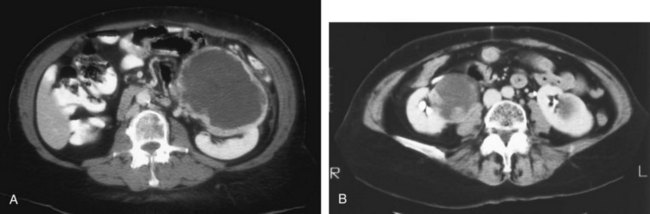

A dedicated (thin-slice) renal CT scan remains the single most important radiographic test for delineating the nature of a renal mass. CT, with and without the administration of contrast material, is necessary to take full advantage of the contrast enhancement characteristics of highly vascular renal parenchymal tumors (Davidson et al, 1997; Zagoria, 2000, Prasad et al, 2008; Ng et al, 2008; Zhang et al, 2007a). In general, any renal mass that enhances with intravenous administration of contrast material on CT by more than 15 Hounsfield units (HU) should be considered an RCC until proved otherwise (Fig. 49–2) (Hartman et al, 2004). Solid masses that also have substantial areas of negative CT attenuation numbers (below −20 HU) indicative of fat are diagnostic of AMLs (Nelson and Sanda, 2002). In 10% to 20% of solid renal masses CT findings are indeterminate, and additional testing or surgical exploration is needed to establish a definitive diagnosis. On occasion, CT demonstrates an enhancing renal segment that is isodense with the remainder of the kidney, suggestive of a renal pseudotumor. Renal pseudotumors may be due to a hypertrophied column of Bertin, renal dysmorphism, or an unusually shaped kidney (Bhatt et al, 2007). In this situation, the diagnosis of a pseudotumor can be confirmed by isotope renography with technetium-labeled dimercaptosuccinic acid or glucoheptonate (Fig. 49–3). These isotope studies demonstrate an area of increased density if the mass is a pseudotumor and an area of decreased density if the mass is a cyst or solid tumor (Israel and Bosniak, 2003a).

Figure 49–2 A, Unenhanced CT scan shows solid, right posterior renal mass. B, After administration of the contrast agent, CT scan shows that the mass enhances more than 20 HU and is thus highly suggestive of RCC. This mass was excised and confirmed to be a clear cell renal cell carcinoma.

(Courtesy of Dr. Terrence Demos, Maywood, IL.)